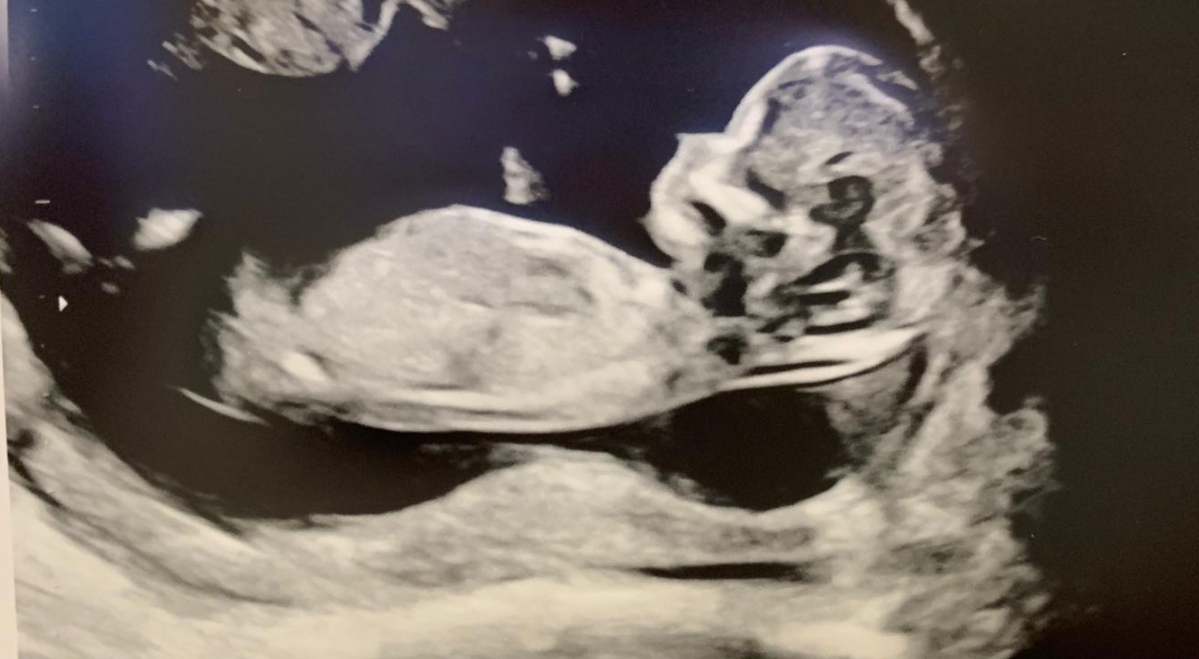

This is NOT me pregnant again :) It is my friend's first baby - who does not mind boy/girl. I guessed girl but im doubting myself xx

This was taken at 14+ weeks

I can't really see the nub here as it looks cut off. Any other pics?

tentative pink lean since it's 14 weeks, though I do think we're missing some of the nub

and that one looks more boy friendly! I guess I'm still 50-50!

Just back to update - this was in deed a girl! (born in June)